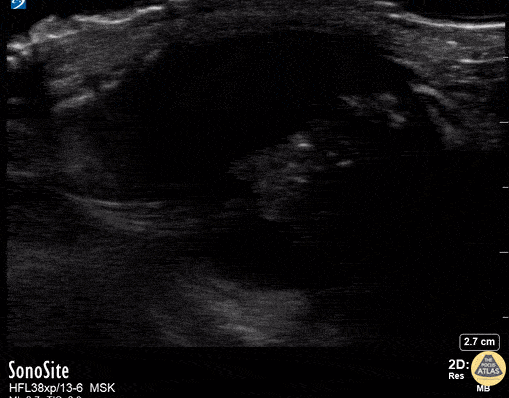

Retinoblastoma in a 3-year-old is noticed on the right side of the clip. Associated retinal detachment on the left side. Contributor: Peter Gutierrez, MD, FAAP Emory University School of Medicine/Children's Healthcare of Atlanta, @pocuspete